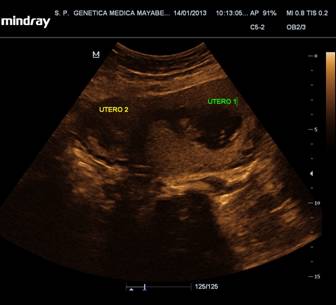

Paciente de 25 años de edad, femenina, raza blanca, universitaria, con antecedentes personales de ser operada al nacimiento de atresia esofágica con fístula traqueoesofágica, y útero doble diagnosticado en edad adulta (figura 2). No antecedentes familiares de defectos congénitos. Al examen físico como rasgos dismórficos se describió una micrognatia.

Fig. 2. Imagen ultrasonográfica del útero doble

Fuente: Archivos de ultrasonografía fetal. Centro Provincial de Genética Médica de Mayabeque

Se realizó ecografía fetal del primer trimestre que fue normal con ductus venoso no patológico y ecografía transvaginal que evidenció el útero doble. Se brindó asesoramiento genético y solicitó estudio cromosómico y diagnóstico prenatal citogenético, recibiendo cariotipo de sangre periférica materna con 46, XX en 12 metafases y cariotipo del líquido amniótico con 46, XX en 16 metafases (ambos normales con resolución de 450 bandas). A las 18 y 20 semanas se realizaron ecografías donde mantenía buen ritmo de crecimiento fetal sin evidencias de defectos congénitos.